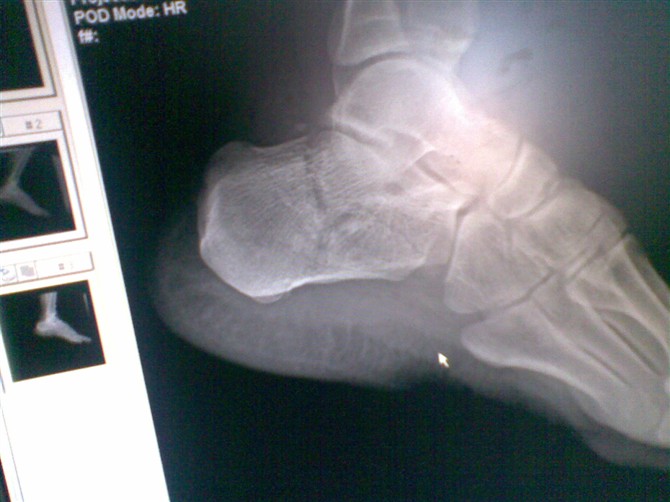

鼻骨外伤   体检气管右移无症状  跟骨骨折望告知轴位摄片的办法[emb18]

鼻骨骨折,胸部未见外伤,跟骨轴位怎么摆你可以查一下投照书。

普通摄片方法就可以满足啊,取坐位,下肢平放,脚尖上翘背伸,足与下肢成直角,机架打30-45度,斜射跟骨就可以了,条件比普通四肢片大一点

病人坐位,脚尖上翘背伸,足与下肢成直角,机架打30-45度,斜射跟骨就可以了,条件比普通四肢片大一点 。如病人因疼痛不能背伸足时,可用繃带兜住脚掌,由患者向上拉,就可以拍照了。

鼻骨骨折,胸部未见明显异常,跟骨轴位投照法可参照6楼意见。